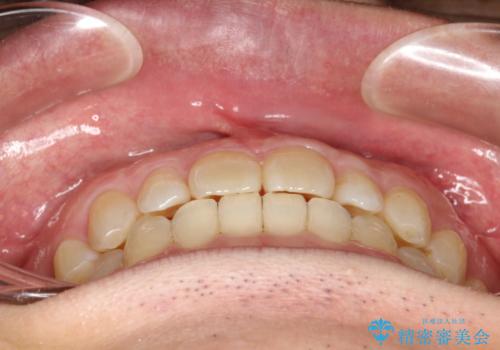

前歯の真ん中の隙間を閉じたい インビザラインによる目立たない矯正

- 上顎の正中の隙間が気になるとのことで来院されました。

下の歯と歯の間をわずかに削り、スペースを作り、正中の隙間を閉じる計画としました。

装置はインビザラインにて行いました。

インビザラインで目立たずに矯正治療を行うことができました。

使用時間を守っていただけたので、比較的スムーズに矯正を終了することができました。